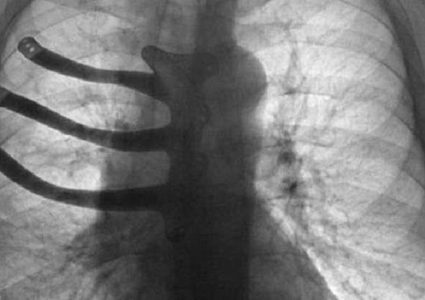

تمكن أطباء موريسون بمدينة سوانسي البريطانية من طبع الجزء المستأصل من القفص الصدري لمريض عمره 71 سنة باستخدام طابعة ثلاثية الأبعاد. اضطر الأطباء إلى استئصال …